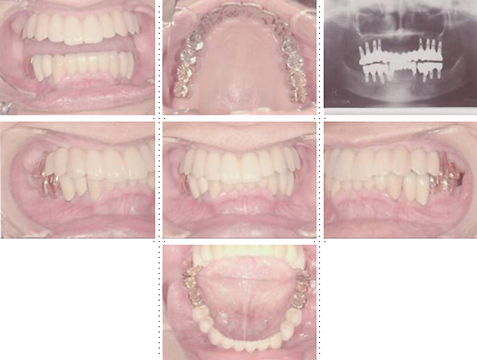

54才 男性

最近はインターネットの情報から来院される方が増えています。インプラント治療に関する知識も豊富で日本中の主だったインプラント歯科医院のホームページをチェックしている方もおります。この方もホームページをご覧になり来院されました。ご自分と同じような症例があり、しかも手術が短時間で痛みが無いのが選択理由だったようです。顎骨の質・量ともに十分でインプラント埋入は簡単です。CT撮影後、インプラント埋入シュミレーションソフトを使用すれば埋入はそれ程難しくはありません。ただ上顎の骨吸収がかなりあり歯の配列がとても難しいケースでした。

症例7

69才 女性

上顎骨がかなり減っていて、骨質・骨量共にインプラント治療には難しいケースです。

CT撮影後、埋入シュミレーションソフトで十分に検討します。このようなケースを成功させるには、患者さんの理解と協力が必要です。 下顎前歯が前突している為、抜髄しポーセレン冠で内側に配列。上顎前歯部・小臼歯部付近は骨幅が狭く、苦肉の策としてミニインプラントを使用。インプラントアバットメントの平行性、前歯の配列を考えると一般的には床を付けたインプラント義歯となります。装着感、審美性を考慮してブリッジにこだわりました。